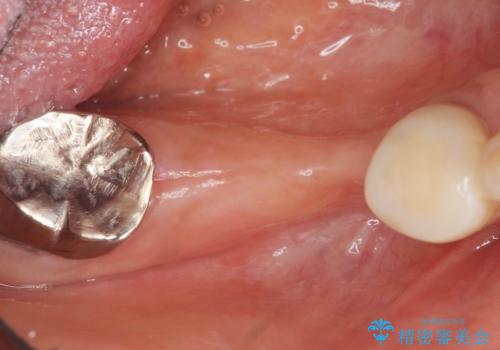

精査したところ、右下4の根尖病変及び右下5の欠損を認め、右下6は残根となり保存不可能な状態でした。

保存不可能な歯を抜去後、インプラント治療と根管治療を行いました。